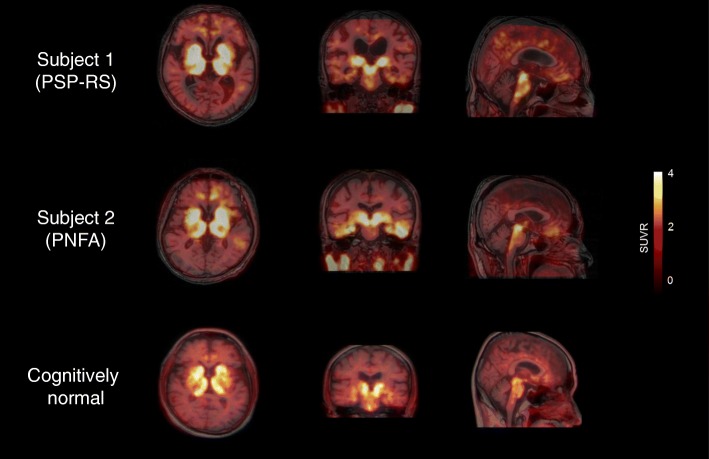

Figure 1 shows the [18F]THK5351 PET images from the two subjects. Images from a cognitively normal individual are shown for comparison at the bottom (Fig. 1). Subject 1 showed significant [18F]THK5351 retention in the globus pallidus and midbrain. Mild tracer retention was observed also in the other cortices, including parahippocampal and inferior temporal gyri. Subject 2 showed prominent [18F]THK5351 retention in the parahippocampal and inferior temporal gyri, as well as the globus pallidus and midbrain. No remarkable retention of [11C]PiB was observed in the neocortex in both of the subjects (data not shown).

Fig. 1.

[18F]THK5351 PET images from two study subjects and a cognitively normal subject. The scale indicates SUVR range from 0 to 4